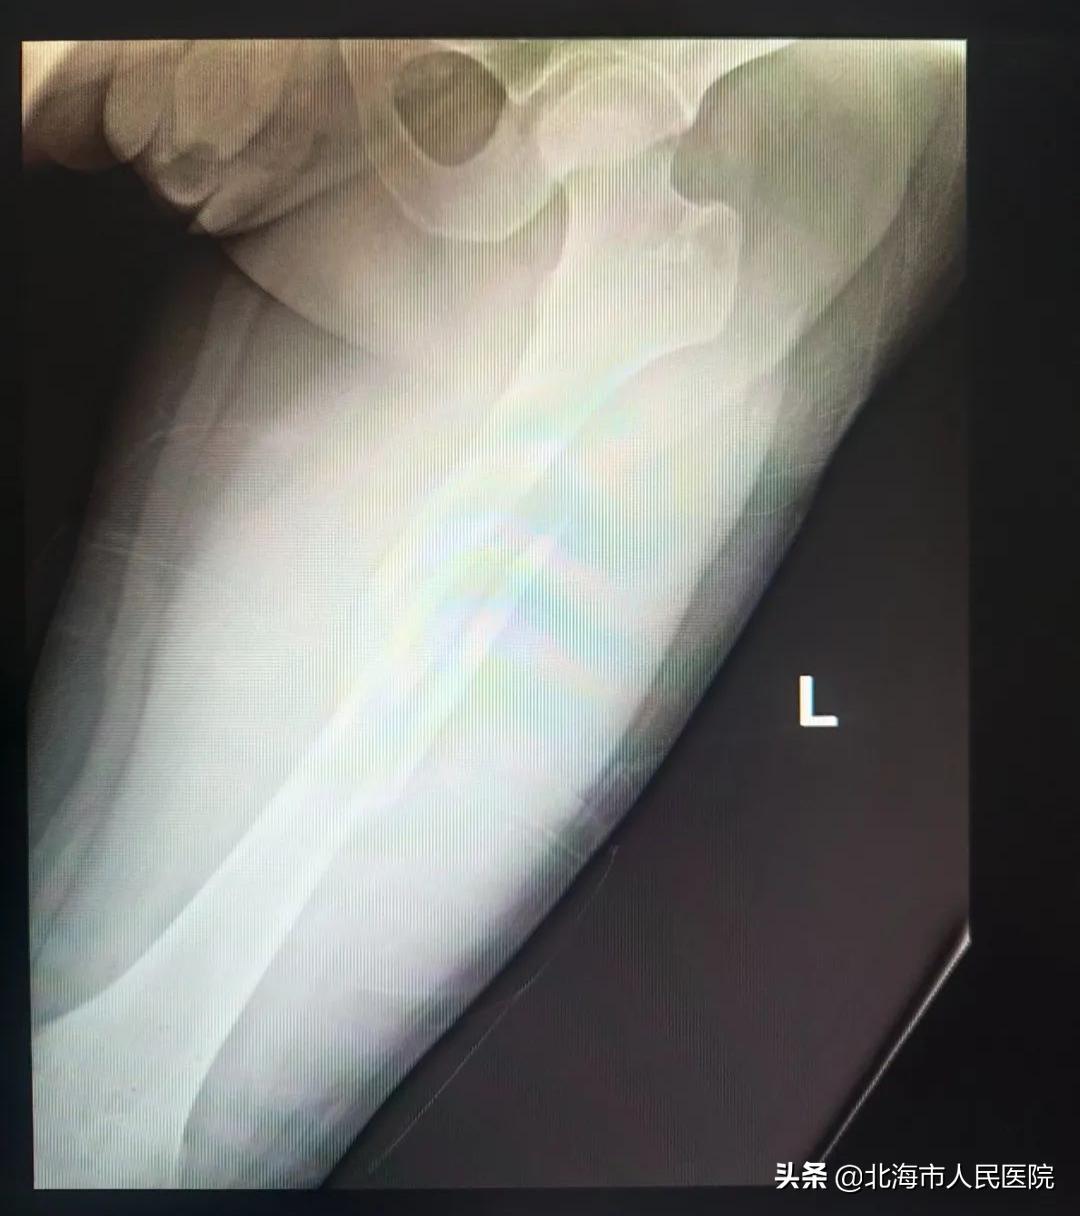

来到急诊科后,医务人员为其注射止痛针,过床拍X线片,提示” 左股骨中段粉碎性骨折,骨折断端错位 “。

11日凌晨0时30分,小姚办理好入院手续,收入创伤手外骨科,张均锦为患者进行皮牵引、冰敷、消肿止痛。12日完善三维CT和血管彩超检查,13日伤后的第三天上午,张均锦为小姚进行微创内固定手术。